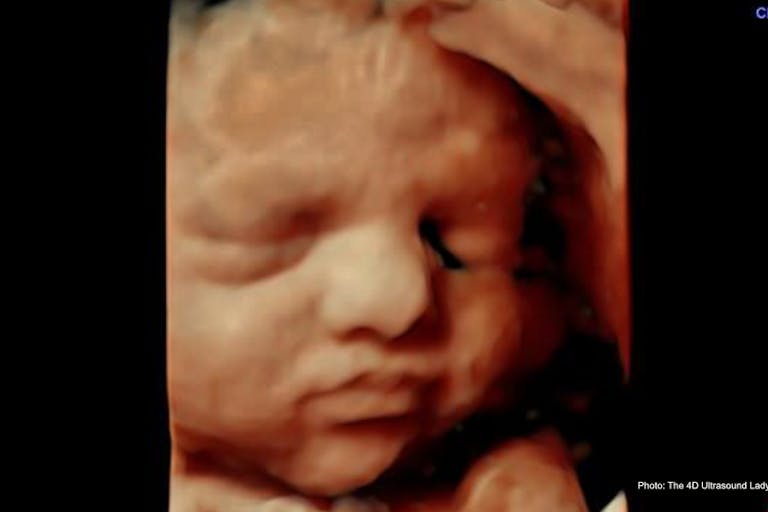

Such a ruling indicates that the decision has less to do with the girl’s health and more to do with her alleged low IQ and the rape. At 33 weeks, her baby has a 95% chance of survival. The only difference between an induction abortion at that stage of pregnancy and an induction delivery is the goal of the procedure. In an induction abortion, the goal is to ensure the baby is dead before delivery, while the goal of induction of labor would be to protect both the baby’s and the mother’s health and life.